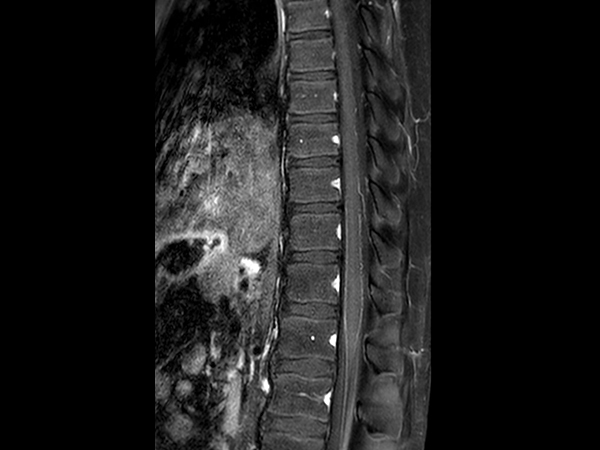

Sagittal STIR TSE